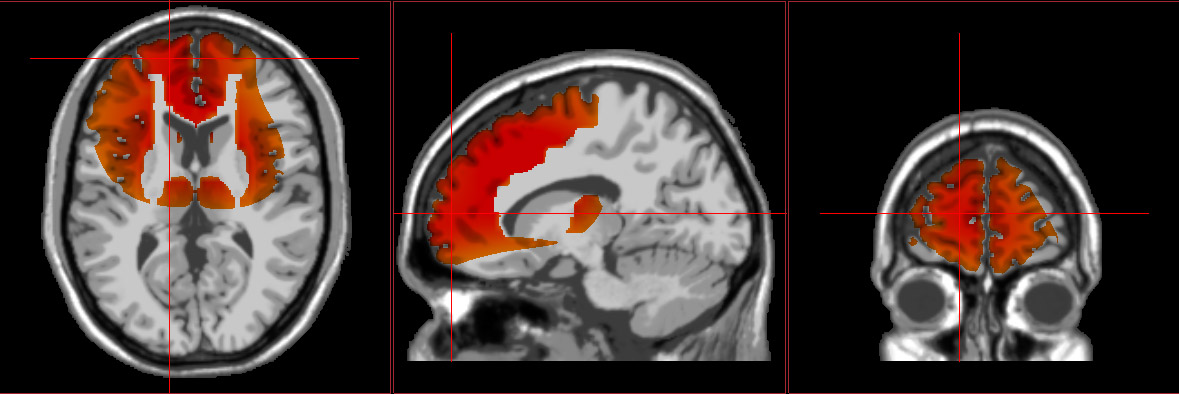

In order to successfully execute all that is required of students, the brain is continuously communicating, integrating, consolidating, activating, and regulating. When students are in class or sitting down to study, different brain regions work together to (ideally) help the student focus their attention, weed through the information, encode what’s important, and store/recall that information correctly. For example, the temporal lobes and visual cortex process what the student is hearing and seeing, the parietal lobes integrate that information with prior learning to make sense of it, the cingulate cortex directs attention toward or away from relevant/irrelevant information and sensations, the hippocampi are responsible for proper storing of new information (i.e., memory and learning), and the prefrontal cortex assists with problem solving, abstract thought, organization, planning, memory recall, determining how to behave appropriately. If any one of these regions is not functioning properly, it can significantly impacts students’ ability to perform well in school.

brain grphic with Brodmann map sw loretta neurofeedback graphic

Extensive neuroimaging research continues to provide more and more information around underlying neurophysiological activity related to attention and learning difficulties, as well as mood and behavioral disorders. As part of our assessment process, we also compare each student’s functional brain imaging against a database of high-functioning individuals their age. This shows us what the student’s brain needs to do in order for the student to do what they need to do. This may include correcting communication errors (whether it be too much or too little communication) between regions, modulating electrical activity, activating regions that are under-firing, and calming down overly excited areas.

Here at NeuroGrove, we utilize advanced forms of 3D functional neuroimaging to see exactly where and how each client’s brain might be impaired and thus be able to get directly to the root of the issue. We then use this information to develop targeted, individualized programs for each client to aid neurophysiological recovery and optimize cognitive function in the most efficient, effective manner possible. This may involve advanced brain-computer interface technology (e.g., swLORETA neurofeedback), transcranial neurostimulation, biofeedback, somatic therapies, personalized nutrition, supplementation to reduce inflammation and aid neurogenesis, wellness coaching, and/or integrative psychotherapy.